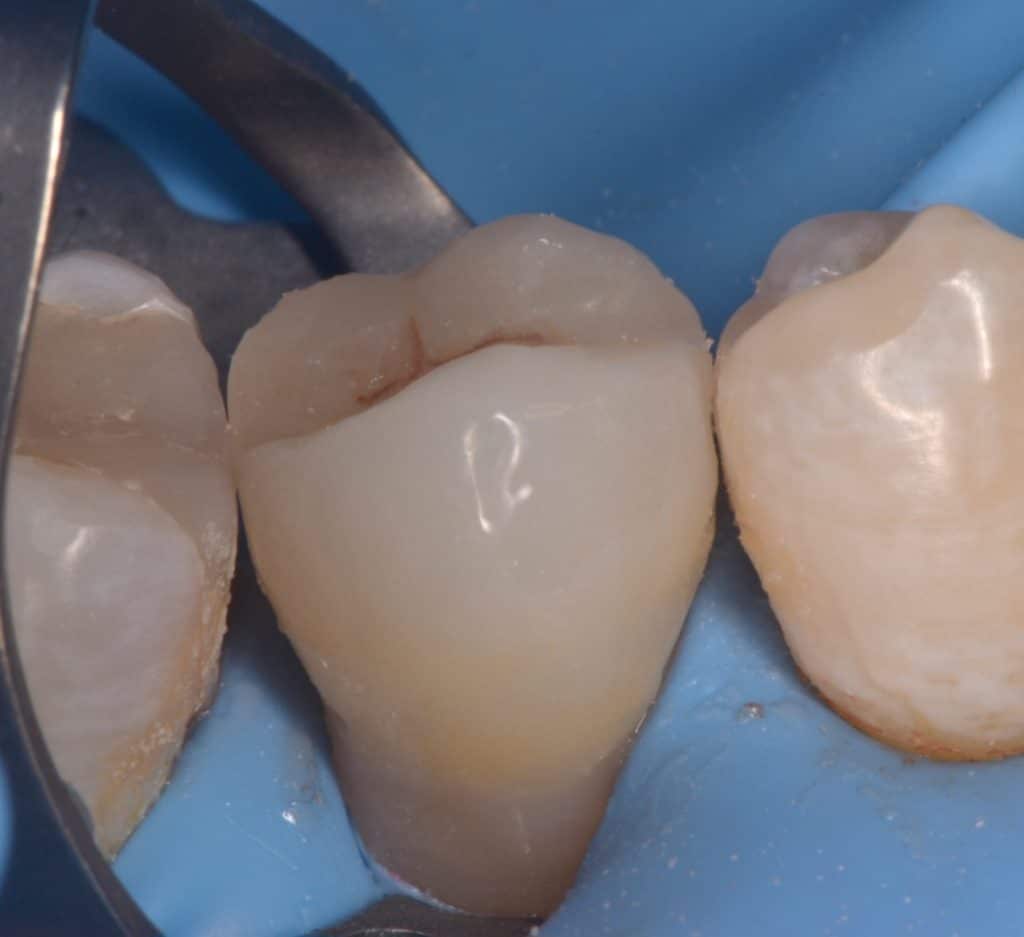

Buccal view showing the same destruction of the tooth, the patient insisted on restoring her tooth

Isolation, look to the amount of tooth structure left under the gingival tissue, dentin quality looks good for bonding, so lets go with adhesive dentistry